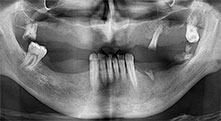

Could you give us a few surgical tips and tricks from your hospital?

Bratu: We like to use the sandwich technique for augmentation in the lateral mandible. A bone cover is prepared with the piezo saw and the crestal fragment is fixed with microscrews. We place a mixture of autologous bone and xenogenic bone replacement material in between. This works very reliably. You should always ensure sufficiently dimensioned vertical cuts when splitting the alveolar ridge in the mandible. Otherwise the bone may fracture easily.